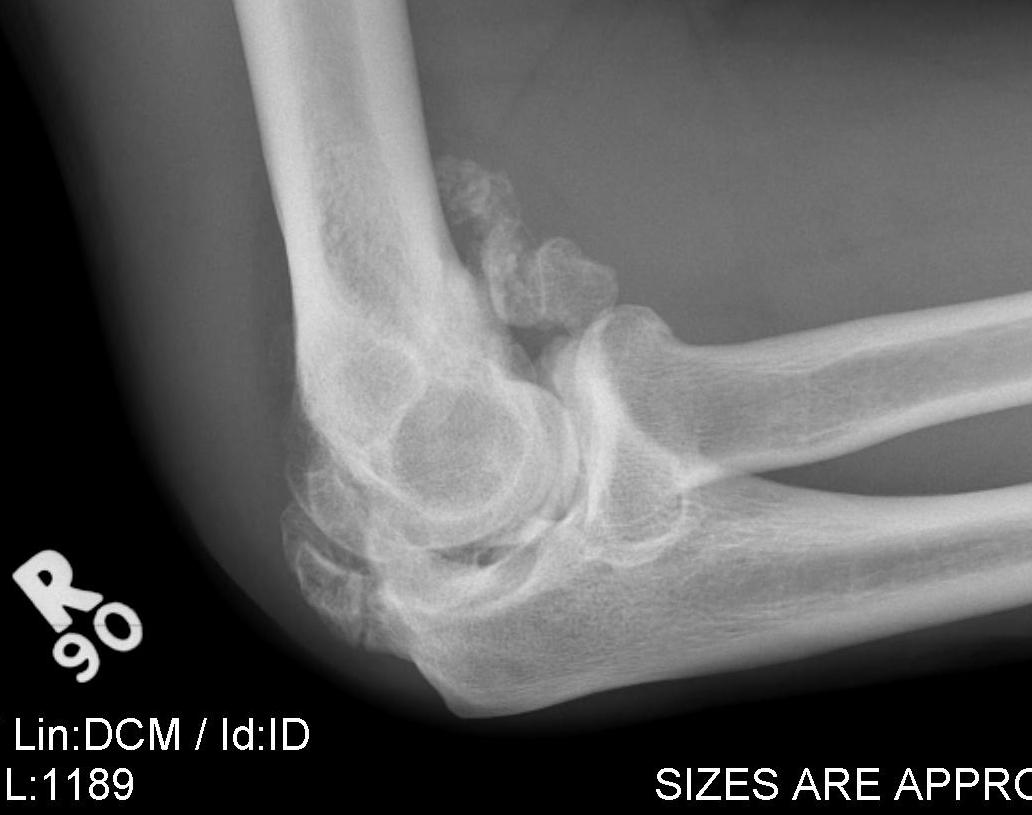

Trauma

- elbow fracture / dislocation

X-ray

Changes occur 2-4 / 52 after injury

Initial cotton candy appearance

- then osseous in appearance

- not attached to bone

- can be resorbed

Mature bone peripherally

DDx

MO

- diaphyseal (OS metaphyseal)

- intact cortex (OS fractures)

- mature bone peripheral with central fibrous tissue (OS mature centrally)

- pain and swelling improves with time (OS worsens)

- normal osteoblast on biopsy